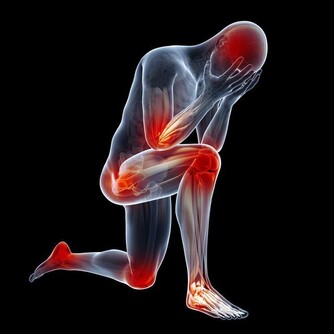

人們產生各種情緒很正常,但如果負面情緒持續時間過長,就會影響健康,

可因此引發抑鬱、焦慮等精神類疾病,甚至誘發多種器質性病變。教你找到壞情緒的根源,分分鐘化解它們。